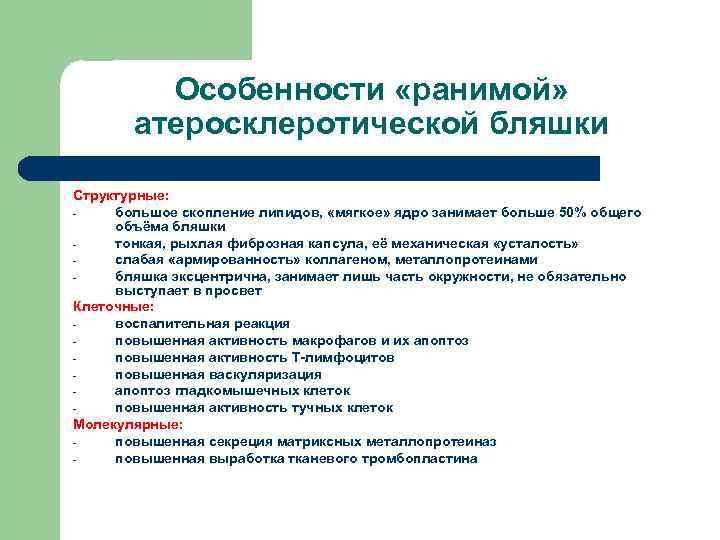

Особенности «ранимой» атеросклеротической бляшки Структурные: большое скопление липидов, «мягкое» ядро занимает больше 50% общего объёма бляшки тонкая, рыхлая фиброзная капсула, её механическая «усталость» слабая «армированность» коллагеном, металлопротеинами бляшка эксцентрична, занимает лишь часть окружности, не обязательно выступает в просвет Клеточные: воспалительная реакция повышенная активность макрофагов и их апоптоз повышенная активность Т-лимфоцитов повышенная васкуляризация апоптоз гладкомышечных клеток повышенная активность тучных клеток Молекулярные: повышенная секреция матриксных металлопротеиназ повышенная выработка тканевого тромбопластина